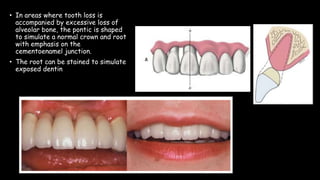

The document discusses pontic design for fixed dental prostheses. It covers pretreatment assessment of residual ridge contours, classifications of ridge deformities, surgical modification techniques, and ideal requirements for pontics. Pontic designs are classified based on their shape and materials. Factors in pontic selection include esthetics and oral hygiene. Common designs for anterior and posterior regions are described, including sanitary, ovate, and saddle pontics. Biological considerations for pontic design involve maintaining the residual ridge, abutment teeth, and supporting tissues.